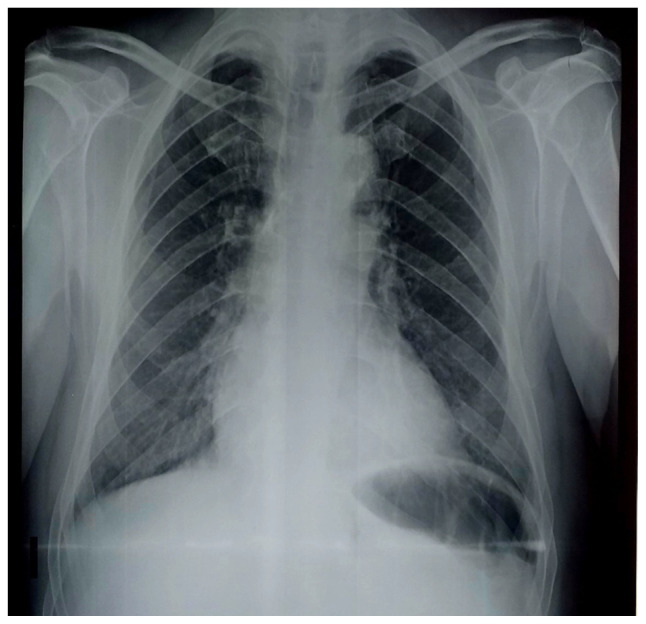

Unexpected porcelain aorta is a real challenge to safely completing aortic valve replacement combined with coronary artery surgery. This condition often leads to an aborted sternotomy in the hope of performing transcatheter procedures, the feasibility of which may be hampered by anatomical considerations. We report the case of a 71-year old man with history of hypertension, type 2 diabetes mellitus and chronic kidney disease, which was referred for severe aortic valve stenosis and severe coronary artery disease. He benefited from an anaortic off-pump coronary surgery and clampless aortic valve replacement under hypothermic circulatory arrest to overcome an unexpected porcelain aorta.